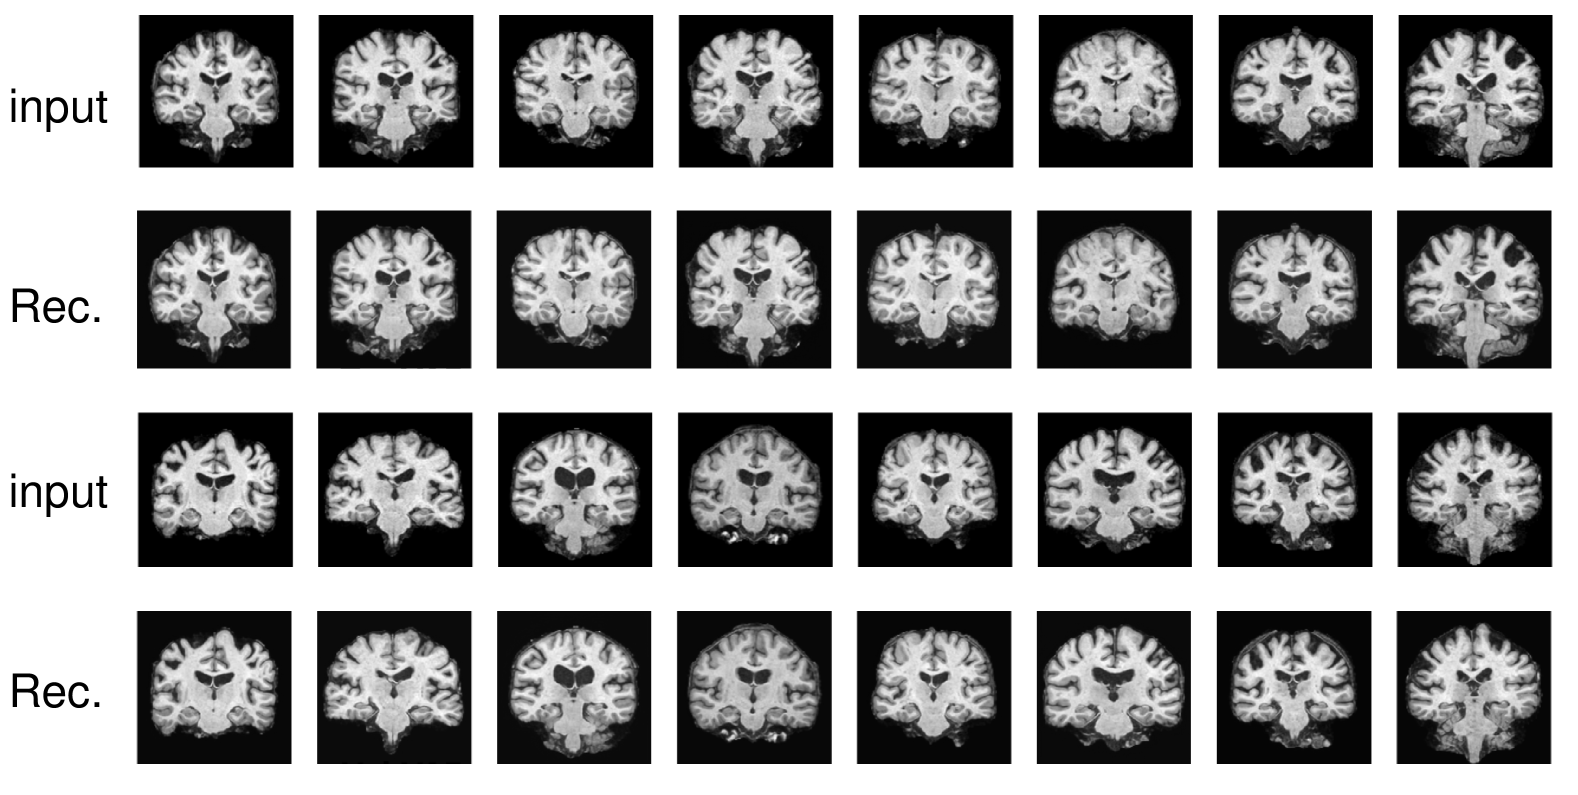

Appendix A AE Training and Reconstruction Results

Refer to caption

Figure 4: Inputs and reconstructions of VAE trained on Baby Brain. The first and third rows display the input baby brain MR images. The second and fourth rows show the reconstructed baby brain images.

Figure 5: Inputs and reconstructions of VAE trained on OASIS-3. The first and third rows display the input OASIS-3 brain MR images. The second and fourth rows show the reconstructed OASIS-3 brain images.

In Fig. 4 and Fig. 5, we show the reconstruction results of our VAE model. The results in the figure suggest that our VAE model can faithfully reconstruct the input images. From the figure, we can observe that the VAE is able to reconstruct brain images at different developmental stages of infants. This observation aligns with the known characteristic that infant brain images are usually less defined at younger ages and become sharper as the infant grows [1].